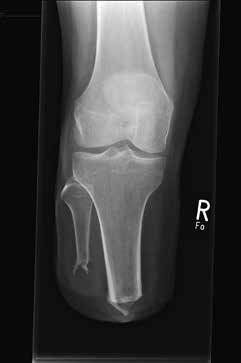

Die Länge des Knochens ist für die Biomechanik des Stumpfes wesentlich verantwortlich. Sie richtet sich nach der Beschaffenheit der Weichteile und der Durchblutung des Unterschenkels. Vom Knochen wird prinzipiell nicht das Periost entfernt. Die Tibia wird ventral angeschrägt, so dass besonders bei kürzeren Stümpfen noch eine breite Endkontaktfläche (Spongiosa) verbleibt (Abb. 13). Im distalen Bereich (langer US-Stumpf), also im Röhrenknochenanteil, sollte man die Knochenkanten gut brechen, damit kein zusätzlicher Druck von innen gegen die dort geringen Weichteile (Haut, Sehnen) herrscht.